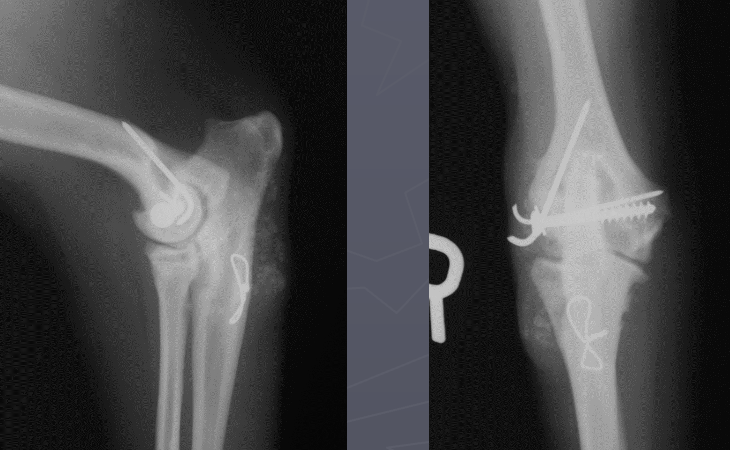

What is shown in these radiographs?

dystrophic mineralization at the level of an elbow joint repair